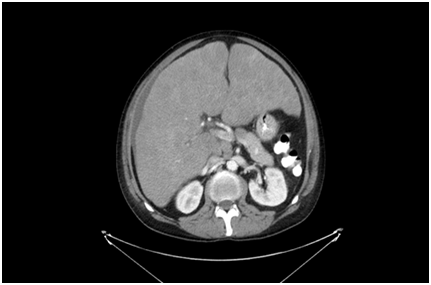

SCLC Comprise about 25 % of all lung cancers. They mostly appear as hilar masses on chest x-ray. Approximately 70% initially present with extensive stage disease.

The pointers in the case were the characteristic chest x-ray, smoking history and imaging of the liver.

Chest X-ray

Figure 1

Figure 1 Chest X-ray.